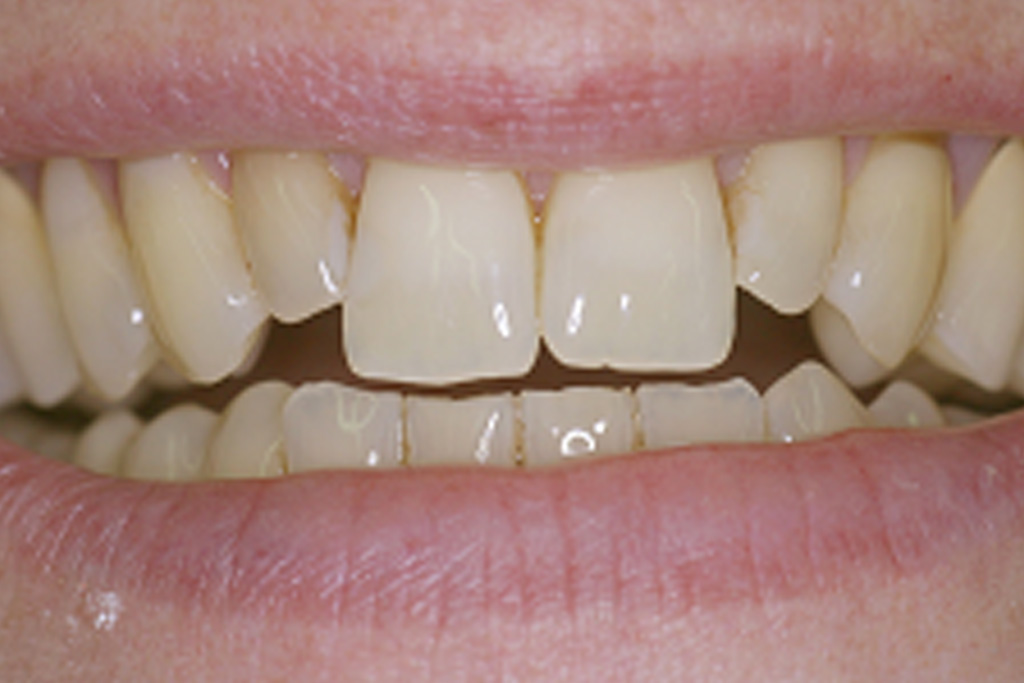

Die präzise Darstellung präparierter Zahnstümpfe auf dem zahntechnischen Meistermodell stellt auch heute noch eine der wichtigsten Schnittstellen zwischen Zahnarzt und Zahntechniker dar. In der Produktionskette hin zur fertigen Krone nimmt dabei der Zahnarzt eine entscheidende Schlüsselstellung ein. Nur er kann durch seine reproduzierbare und präzise Abformmethodik die Voraussetzung für ein perfektes Modell schaffen und damit Passungenauigkeiten der anzufertigenden Krone vermeiden. Dies ist besonders deshalb wichtig, weil Passungenauigkeiten an Kronenrestaurationen (Über- und Unterextension des Kronenrandes, übergroßer Randspalt ) häufig eine Fülle perioprothetischer und ästhetischer Probleme verursachen (Abb.1 ) :

Da die Präparationsgrenze bzw. der Präparationsrand in der Regel 0,5 bis 1,5 mm unterhalb des Zahnfleischrandes (= subgingival ) verläuft, wird zumeist während der Präparation des Zahnes das Zahnfleisch verletzt. In der Folge tritt eine verstärkte Blutung am Zahnfleischrand (= Sulkus) auf.

Bei der anschließenden Abformung der präparierten Zahnstümpfe bestehen zwei Probleme (Abb2.) . Zum Einen muss das den Zahn umgebende Weichgewebe vom Präparationsrand abgedrängt werden (= Retraktion) und zum Anderen darf während der Abformung kein Blut auf die abzuformende Zahnoberfläche gelangen. Unzureichende Retraktion und Blutungen im Sulkus verhindern eine präzise Abformung. Die Abformung muss wiederholt werden.

Mit Hilfe des Lasers können heute erstmals diese beiden. Hauptprobleme bestmöglich in den Griff bekommen werden.

Der Laser verdampft punktuell störende Gewebeanteile im Sulkus und stoppt gleichzeitig durch seine blutungsstillende Wirkung die Gewebeblutung . Dabei ist die Gewebeschädigung (=Trauma) minimal. Durch diese minimaltraumatisierende Wirkung ist die anschließende Wundheilung wesentlich schmerzärmer als bei der früher üblichen elektrochirurgischen Abtragung. Im Zuge der Heilung ist die Schrumpfungstendenz des Zahnfleischrandes zudem erheblich geringer. Dies fördert das ästhetische Erscheinungsbild der eingegliederten Krone im Zahnhalsbereich, da der Kronenrandbereich unterhalb des Zahnfleischrandes verbleibt (Abb. 3 ).

im Bereich der Vollkeramikkronen an den Oberkieferfrontzähnen 13-23